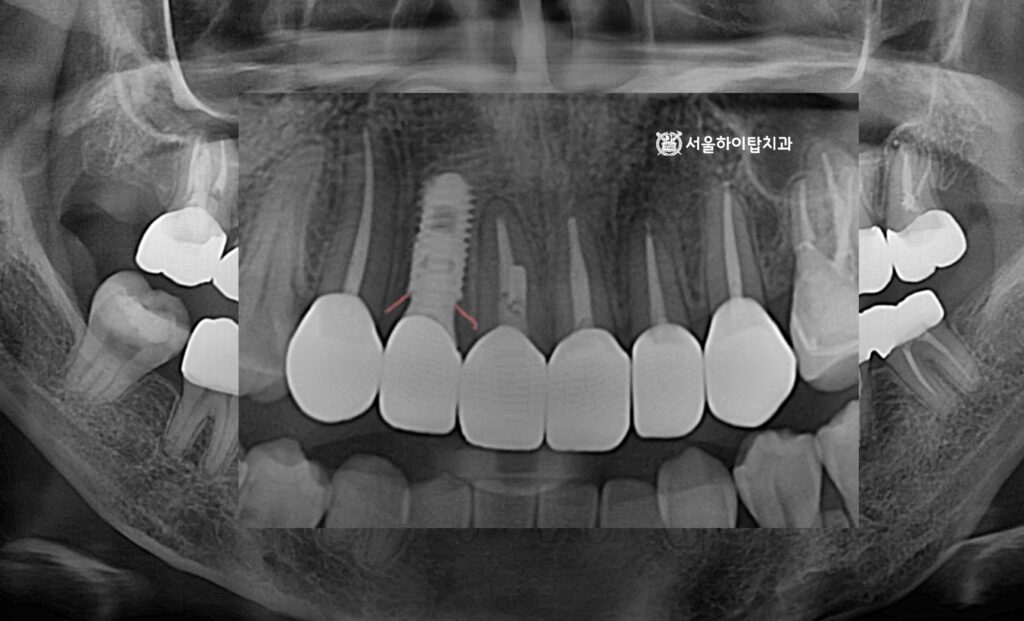

위 엑스레이 사진을 살펴보면,

전치부 치아 특성상 치조골 폭이 다소 좁음에도 불구하고,

앞서 진행한 가상 시뮬레이션을 기반으로 안전하고 정확한 위치에

임플란트가 식립된 모습을 확인할 수 있습니다.

백운역 치과 에서 PA 사진으로 확인해도,

주변 인접 치아나 치주 조직에 손상 없이 정확하게 식립된 모습을 확인할 수 있습니다.

파노라마 엑스레이에서도, 픽스처가 골 속에 단단히 심겨져

안정적인 모습을 확인할 수 있으며,

주변 치아와도 조화로운 배열을 이루고 있음을 확인할 수 있습니다.